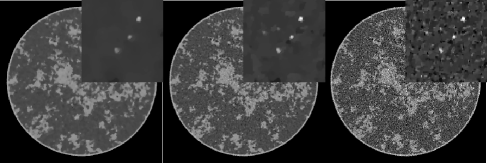

To appreciate the impact of , we focus on the 512-view data set and display images in Fig. 4 for three cases. Small corresponds to a tight data constraint, resulting in salt-and-pepper noise in the image due to the high noise-level of the data. Increasing reduces the image noise and eventually removes small structures.